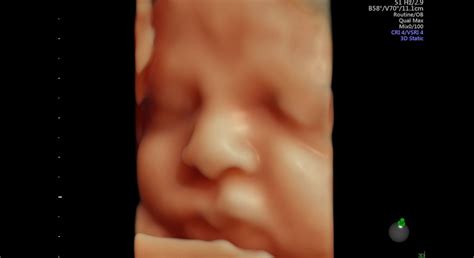

3D alebo 4D zobrazenie dieťatka sa nevykonáva zo zdravotných dôvodov, no cieľom je získať peknú pamiatku na tehotenstvo a spoznať napríklad tváričku drobčeka. Najčastejšie sa 3D alebo 4D ultrazvuk robí od 24. do 30. týždňa tehotenstva - dieťatko už je obalené tukovou vrstvou a jeho tvár nesie presne tie črty, aké bude mať aj po narodení. Samozrejmosťou je, že sa lekár pozrie aj na pohlavie.